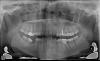

bliss Опубликовано 25 марта, 2010 Поделиться Опубликовано 25 марта, 2010 Здравствуйте. Дайте совет по следующим зубам:1. Шестой справа наверху. Год назад были запломбированы каналы. Недавно стал слегка беспокоить при накусывании. В чем может быть проблема? Надо ли перелечивать каналы? 2. Шестой слева снизу. Лечили года 4 назад. Ни разу не беспокоил, сегодня сказали что надо перелечивать каналы и так оставлять нельзя. 3. Пятый слева наверху (со штифтом). Запломбированы ли там каналы? Что с ним лучше делать: лечить каналы и коронка или что-то еще? Панарамный снимок Шестой справа наверху Ссылка на комментарий

Андрей Опубликовано 26 марта, 2010 Поделиться Опубликовано 26 марта, 2010 Шестой справа наверху, что с ним не так? В нем нужно все каналы перелечивать?В условиях отсутствия каких-либо стандартов качства лечения можно считать, что этот зуб слелан хорошо, у него запломбированы все четыре канала это большая редкость.Однако, если Вы будете делать на этот зуб коронку, я бы Вам рекомендавал перепломбировать каналы, потомучто по моему мнению они недостаточно расширены.Выгледеть картинка должна как-то так.http://content.foto.mail.ru/list/sablinav/fishing/i-104.jpg Ссылка на комментарий

bliss Опубликовано 26 марта, 2010 Автор Поделиться Опубликовано 26 марта, 2010 В условиях отсутствия каких-либо стандартов качства лечения можно считать, что этот зуб слелан хорошо, у него запломбированы все четыре канала это большая редкость.Однако, если Вы будете делать на этот зуб коронку, я бы Вам рекомендавал перепломбировать каналы, потомучто по моему мнению они недостаточно расширены. Действительно, каналы были очень узкие, проходили их с трудом, в два захода, закладывали лекарства для расширения. Может их ширина это все что можно было сделать или каналы можно расширять неограничено (тоесть пока не будет достигнута нужная ширина)? Еще на консультации было сказанно что в самом длинном канале(который по центру) инфекция и возможно обломок инструмента, это действительно там есть? Ссылка на комментарий

Андрей Опубликовано 26 марта, 2010 Поделиться Опубликовано 26 марта, 2010 Действительно, каналы были очень узкие, проходили их с трудом, в два захода, закладывали лекарства для расширения. Может их ширина это все что можно было сделать или каналы можно расширять неограничено (тоесть пока не будет достигнута нужная ширина)? Еще на консультации было сказанно что в самом длинном канале(который по центру) инфекция и возможно обломок инструмента, это действительно там есть?Безгранично расширять не стоит, а до определенного газмера необходимо. Обломков я не вижу. Ссылка на комментарий